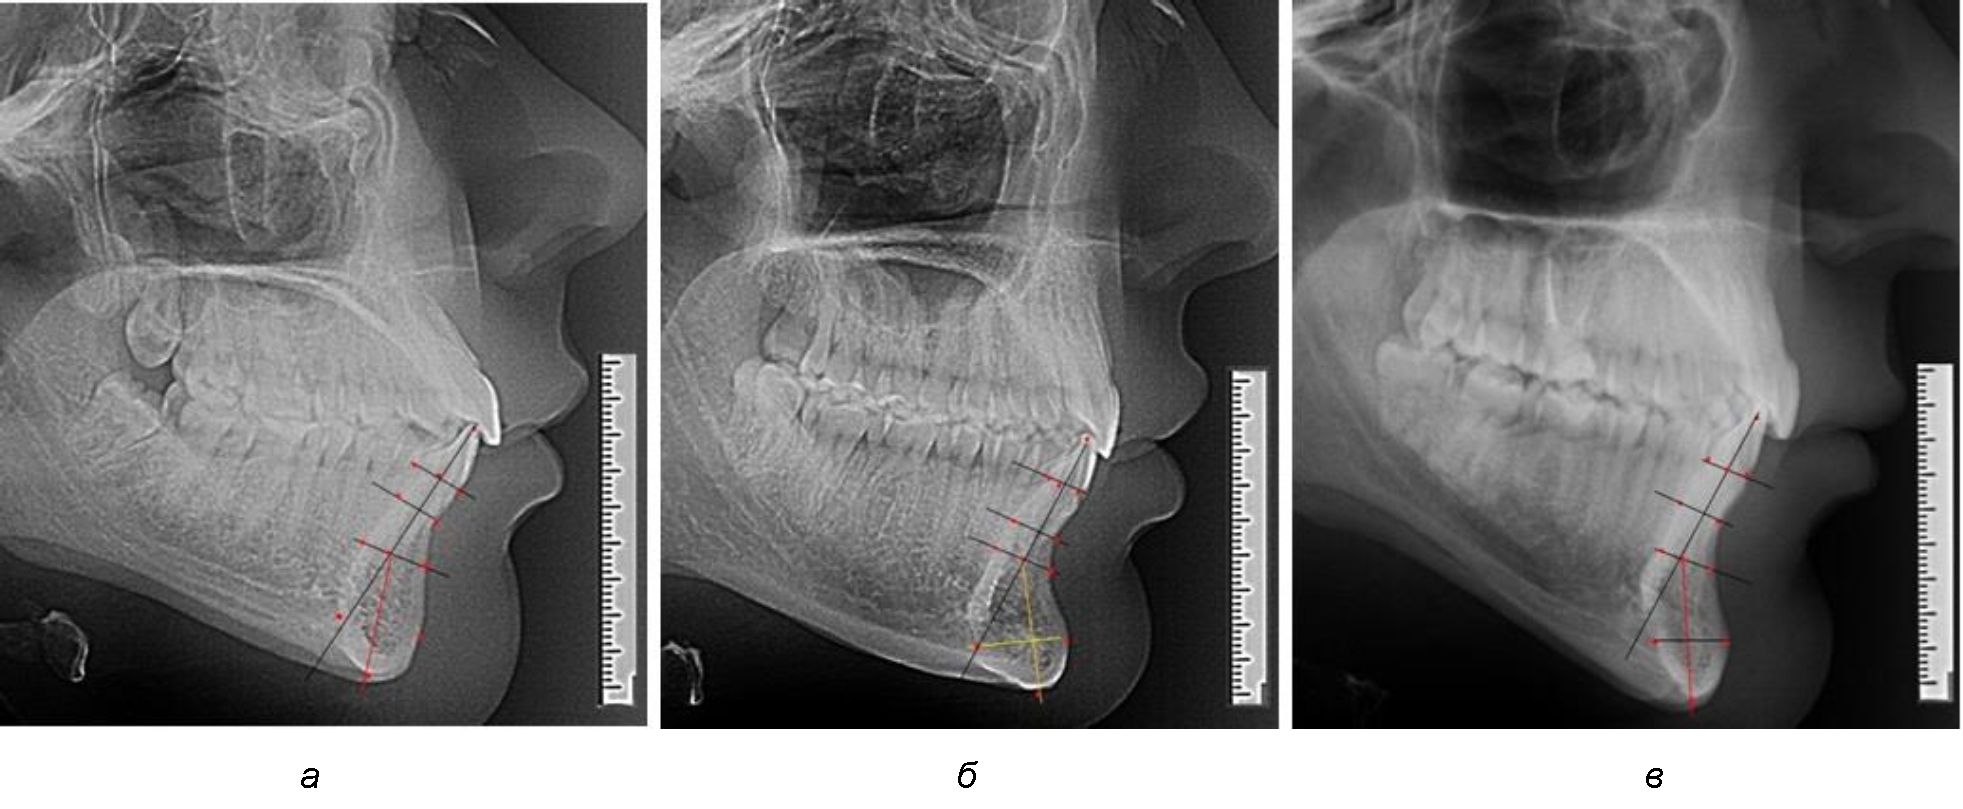

При анализе полученных данных обращает на себя внимание факт того, что из вертикальных параметров зубоальвеолярной части сегмента наиболее вариабельным является размер между апикальными точками Downs и Schwarz (BSM–B), который составлял (6,79 ± 0,54) мм, при величине сигмального отклонения – 2,35. Также большая ошибка репрезентативности и сигмальное отклонение было отмечено при оценки ширины подбородочного выступа. В связи с этим встречались варианты резцовых сегментов нижней челюсти различные как по ширине, так и по высоте, а также по расхождению положения апикальных точек по Downs и Schwarz (рис. 3).

Рис. 3. Варианты среднего (а), широкого (б) и узкого (в) нижнечелюстного резцового сегмента

Так же, как и при исследовании сегментов, обращает на себя внимание факт того, что из вертикальных параметров зубоальвеолярной части сегмента наиболее вариабельным является размер между апикальными точками Downs и Schwarz (BSM–B), который составлял (6,79 ± 0,41) мм, при величине сигмального отклонения 1,78.

Также большая ошибка репрезентативности и сигмальное отклонение было отмечено при оценке ширины подбородочного выступа.

Варианты резцовых сегментов нижней челюсти различные как по ширине, так и по высоте, а также по расхождению положения апикальных точек по Downs и Schwarz представлены на рис. 4.

Рис. 4. Особенности нижнечелюстного резцового сегмента на ТРГ у людей при среднем (а), широком (б) и узком (в) вариантах

Нередко отмечается деформация подбородочного выступа и различное его положение по отношению к зубоальвеолярной части сегмента. При мезиальной окклюзии нередко нижняя подбородочная точка смещается кзади по отношению к условной срединной вертикали нижнего резца, а при дистальной окклюзии отмечается компенсаторное отклонение подбородка кпереди (рис. 5).

Рис. 5. Особенности нижнечелюстного резцового сегмента на ТРГ у людей при мезиальной (а) и дистальной (б) окклюзии

Кроме того, так же как и у людей с физиологической окклюзией, определялось различие в положении апикальных точек Downs и Schwarz, что, по нашему мнению, может определять тактику лечения патологических форм протрузии/ретрузии резцов с учетом биотипа костной ткани.